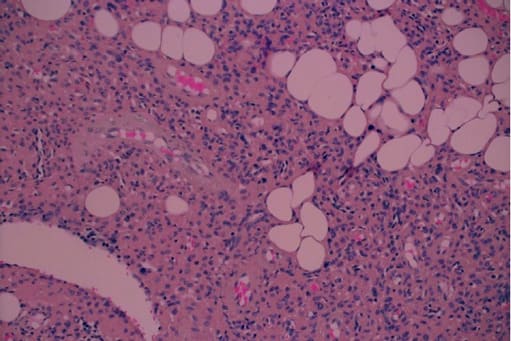

An 81-year-old man who was referred to the endocrinological clinic after he was diagnosed with osteopenia (T score of minus -1.5 in the spine and minus -1.2 in the femur). Five years previously, he was treated by a family physician with alendronate, vitamin D and calcium. He was referred to orthopedic consultation due to intense left hip pain. Upon his arrival he underwent physical examination and pelvic computed tomography (CT), which did not show any pathological findings. Medical history did not disclose any chronic diseases or hereditary bone disease apart from the history of bullet shrapnel fragments in different parts of his body which were the result of past military injuries. Laboratory results disclosed normal calcium levels 9.9 mg/dl (normal range 8.810.20 mg/dl) low phosphorus 2.10 mg/dl (normal range 2.5-5 mg/dl) and mild elevated alkaline phosphatase 144 U/L (normal range 30-120 U/L), 25 hydroxy vitamin D test results were normal, 121 nmol/l (normal range 39-160 pmol/l). The clinical findings which revealed low phosphorus levels and elevated alkaline phosphatase levels, raised our suspicion regarding TIO. FGF23 levels in the blood were elevated to 150.8 pg/ml (normal range 23.2- 95.4 pg/ml). Repeated 24-hour urine phosphate collection disclosed relatively high phosphate excretion 959 mg/24h (normal range 400-1300 mg/dl) (Figure 6). Imaging with 68Gallium DOTANOC PET/CT revealed pathologic uptake in the upper aspect of the left shoulder adjacent to the coracoid process. No mediastinal or axillary lymphadenopathy was observed (Figure 5). The patient was referred to the orthopedic surgical department, due to suspected phosphaturic mesenchymal tumor. Since an MRI could not be performed, because of the remaining bullet fragments in the body, the tumor and its anatomical position were evaluated by an ultrasound examination. After the evaluation, the patient underwent wide resection of the tumor. Histopathological examination of the tumor disclosed fat tissue with proliferation of bland spindle cells with numerous blood vessels, amorphous matrix deposition and several calcifications without atypia and mitosis, with free surgical margins. These findings were consistent with a benign phosphaturic mesenchymal tumor (Figure 7). Three months post-surgery, phosphorus levels and a 24-hour phosphorus collection were normalized.

Figure 7: Microscopic pathological view of the tumor, displaying fat tissue with proliferation of bland spindle cells, numerous blood vessels, amorphous matrix deposition and several calcifications without atypia or mitosis.